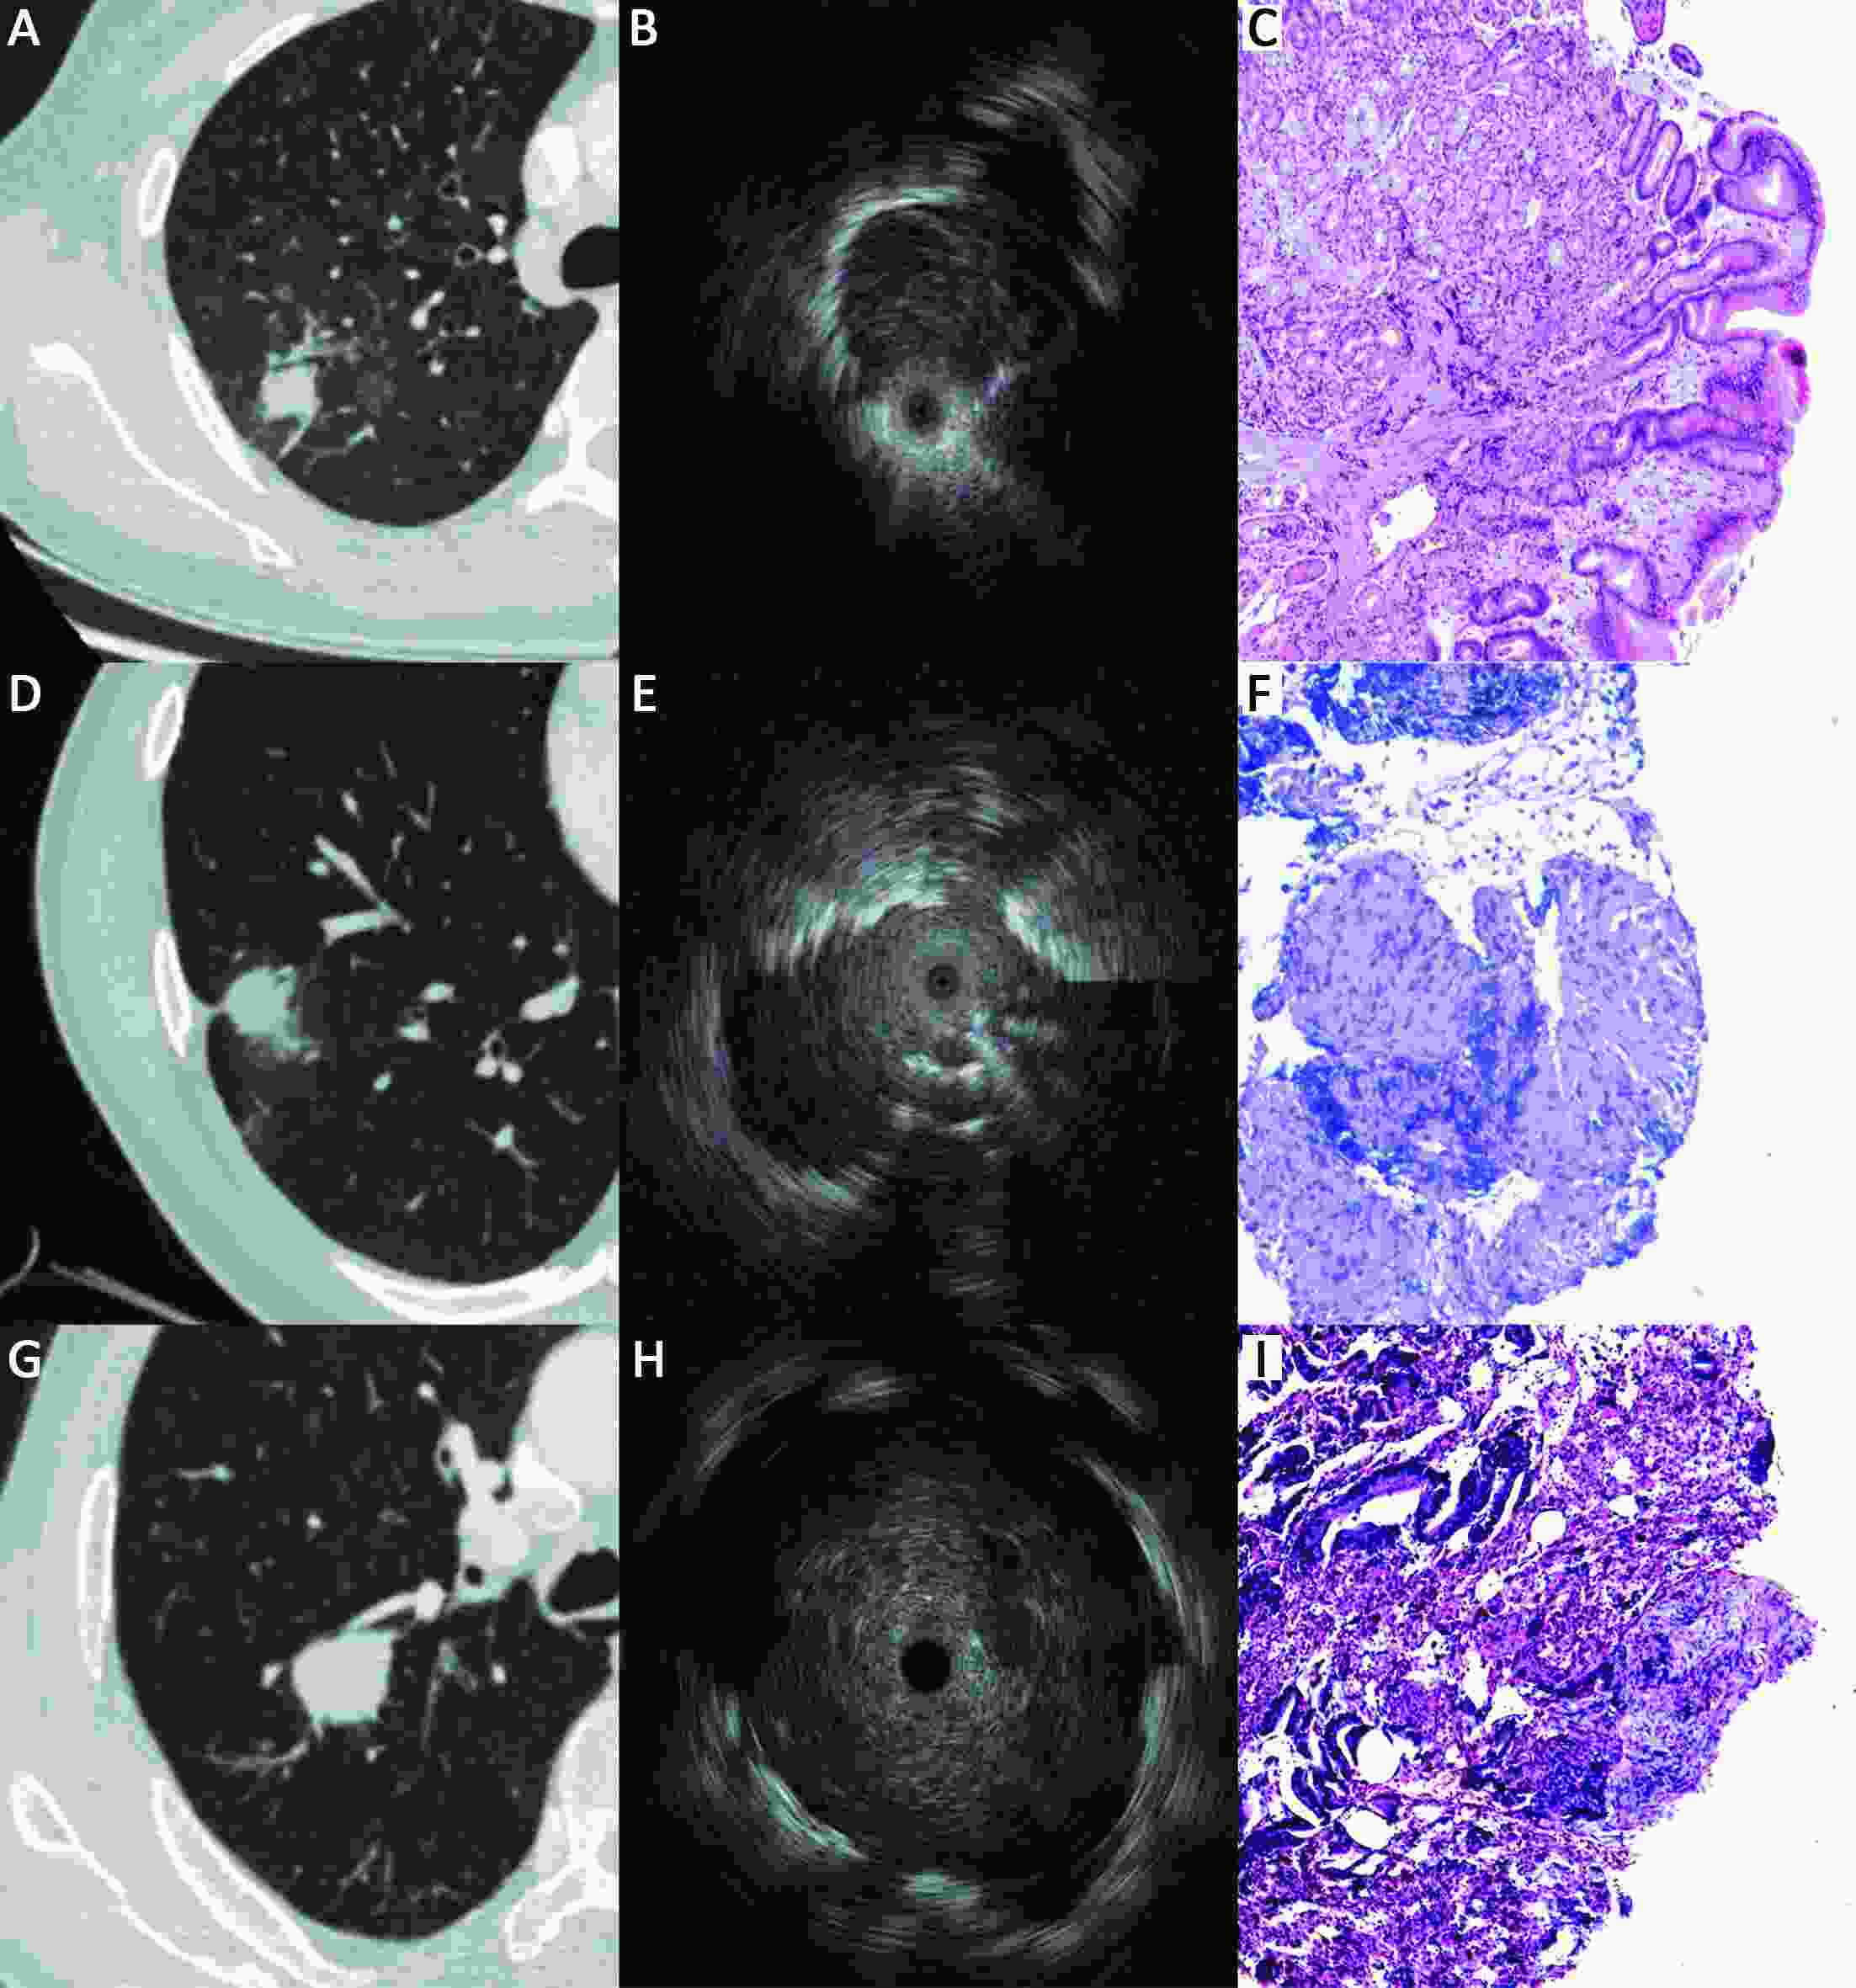

ObjectiveFluoroscopy guidance is generally required for endobronchial ultrasonography with guide sheath (EBUS-GS) in peripheral pulmonary lesions (PPLs). Virtual bronchoscopic navigation (VBN) can guide the bronchoscope by creating virtual images of the bronchial route to the lesion. The diagnostic yield and safety profiles of VBN without fluoroscopy for PPLs have not been evaluated in inexperienced pulmonologist performing EBUS-GS. MethodsBetween January 2016 and June 2017, consecutive patients with PPLs referred for EBUS-GS at a single cancer center were enrolled. The diagnostic yield as well as safety profiles was retrospectively analyzed, and our preliminary experience was shared. ResultsA total of 109 patients with 109 lesions were included, 99 (90.8%) lesions were visible on EBUS imaging. According to the procedure time needed to locate the lesion on EBUS, 24.8% (27/109) were deemed technically difficult procedures; however, no significant relationships were identified between candidate parameters and technically difficult procedures. The overall diagnosis yield was 74.3% (81/109), and the diagnostic yield of malignancy was 83.7% (77/92). Lesions larger than 20 mm [odds ratio (OR), 2.758; 95% confidence interval (95% CI), 1.077−7.062; P=0.034] and probe of within type (OR, 3.174; 95% CI, 1.151−8.757, P=0.026) were independent factors leading to a better diagnostic yield in multivariate analysis. About 30 practice procedures were needed to achieve a stable diagnostic yield, and the proportion of technically difficult procedures decreased and stabilized after 70 practice procedures. Regarding complications, one patient (0.9%) had intraoperative hemorrhage (100 mL) which was managed under endoscopy. ConclusionsVBN without fluoroscopy guidance is still useful and safe for PPLs diagnosis, especially for malignant diseases when performed by pulmonologist without previous experience of EBUS-GS. VBN may simplify the process of lesion positioning and further multi-center randomized studies are warranted.